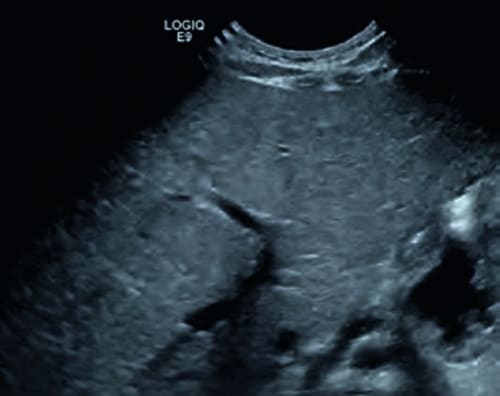

Mittels Ultraschall kann man praktisch alle Körperregionen untersuchen. Besondere Bedeutung hat der Ultraschall bei der Untersuchung des Gehirns. Hier liefert er sehr gute Ergebnisse, da die Schädelknochen noch weit genug auseinander stehen, um ein regelrechtes „Fenster“ für den Ultraschall zu bilden. Bauch- und Brustorgane werden ebenfalls mit Ultraschall untersucht. So kann die normgerechte Entwicklung beobachtet werden und bei ungewöhnlichen Befunden rasch Maßnahmen eingeleitet werden.